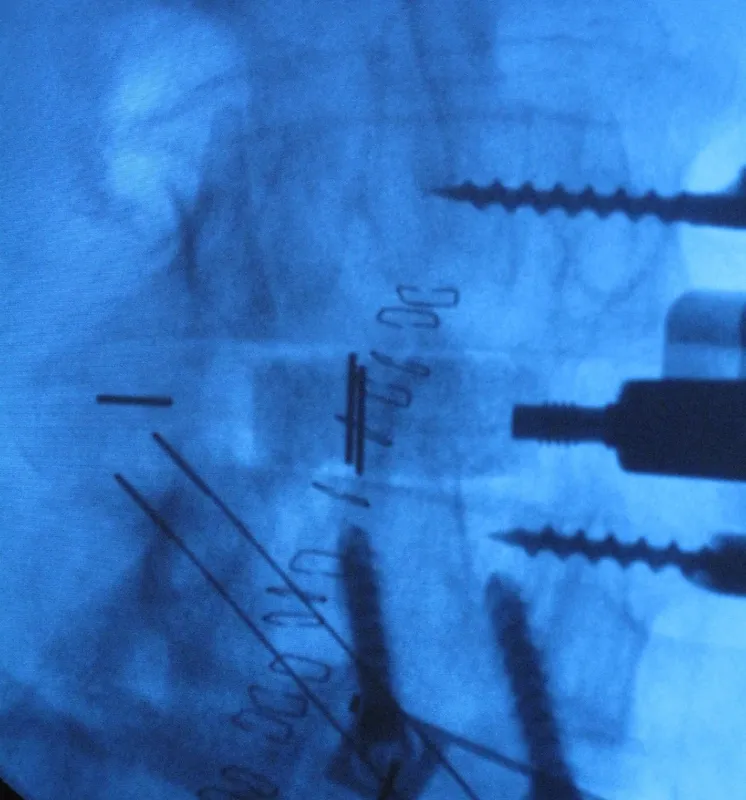

The ‘in theatre’ image shows Inductigraft™ packed into a vertebral spacer. The Inductigraft™ X-ray image reveals the inductigraft in between the two vertebrae.

Inductigraft™ X-ray image